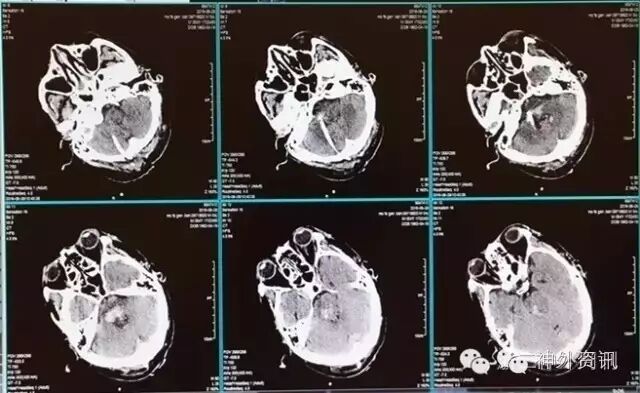

入院时因病情危重,暂予保守对症治疗。至入院第3天,病情尚稳定,家属希望手术再请神经外科立体定向组会诊,会诊意见认为可行立体定向血肿穿刺引流,并告知手术风险及预后等。家属经协商后决定手术,于入院第4天在全麻下行立体定向血肿穿刺引流术(图2,视频1)。

图2. 术前CT,血肿大小基本同术前。